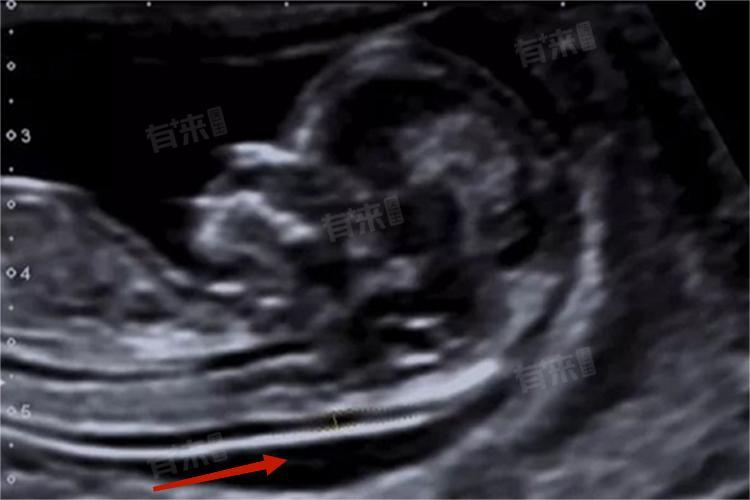

- 小排畸:主要侧重于对胎儿全身各器官的发育情况进行详细检查,包括颅脑、肾、腹部、胸部等关键部位。通过小排畸检查,医生可以更加全面地了解胎儿是否存在畸形或异常情况,如胃肠道畸形、脑部发育异常、骨骼和脊髓问题等。小排畸还具有复核大排畸检查的作用,能够进一步排除在大排畸中可能遗漏的畸形或异常情况。